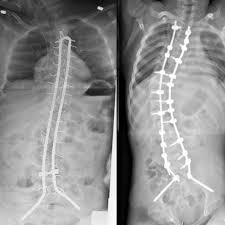

2. التدخل الجراحي:

يُوصى بالجراحة في الحالات المتقدمة، أو عند فشل الطرق غير الجراحية. تشمل:

دمج الفقرات (Spinal Fusion) لمنع تطور الانحناء.

إجراءات مخصصة لتحسين الجلوس والوظيفة التنفسية.